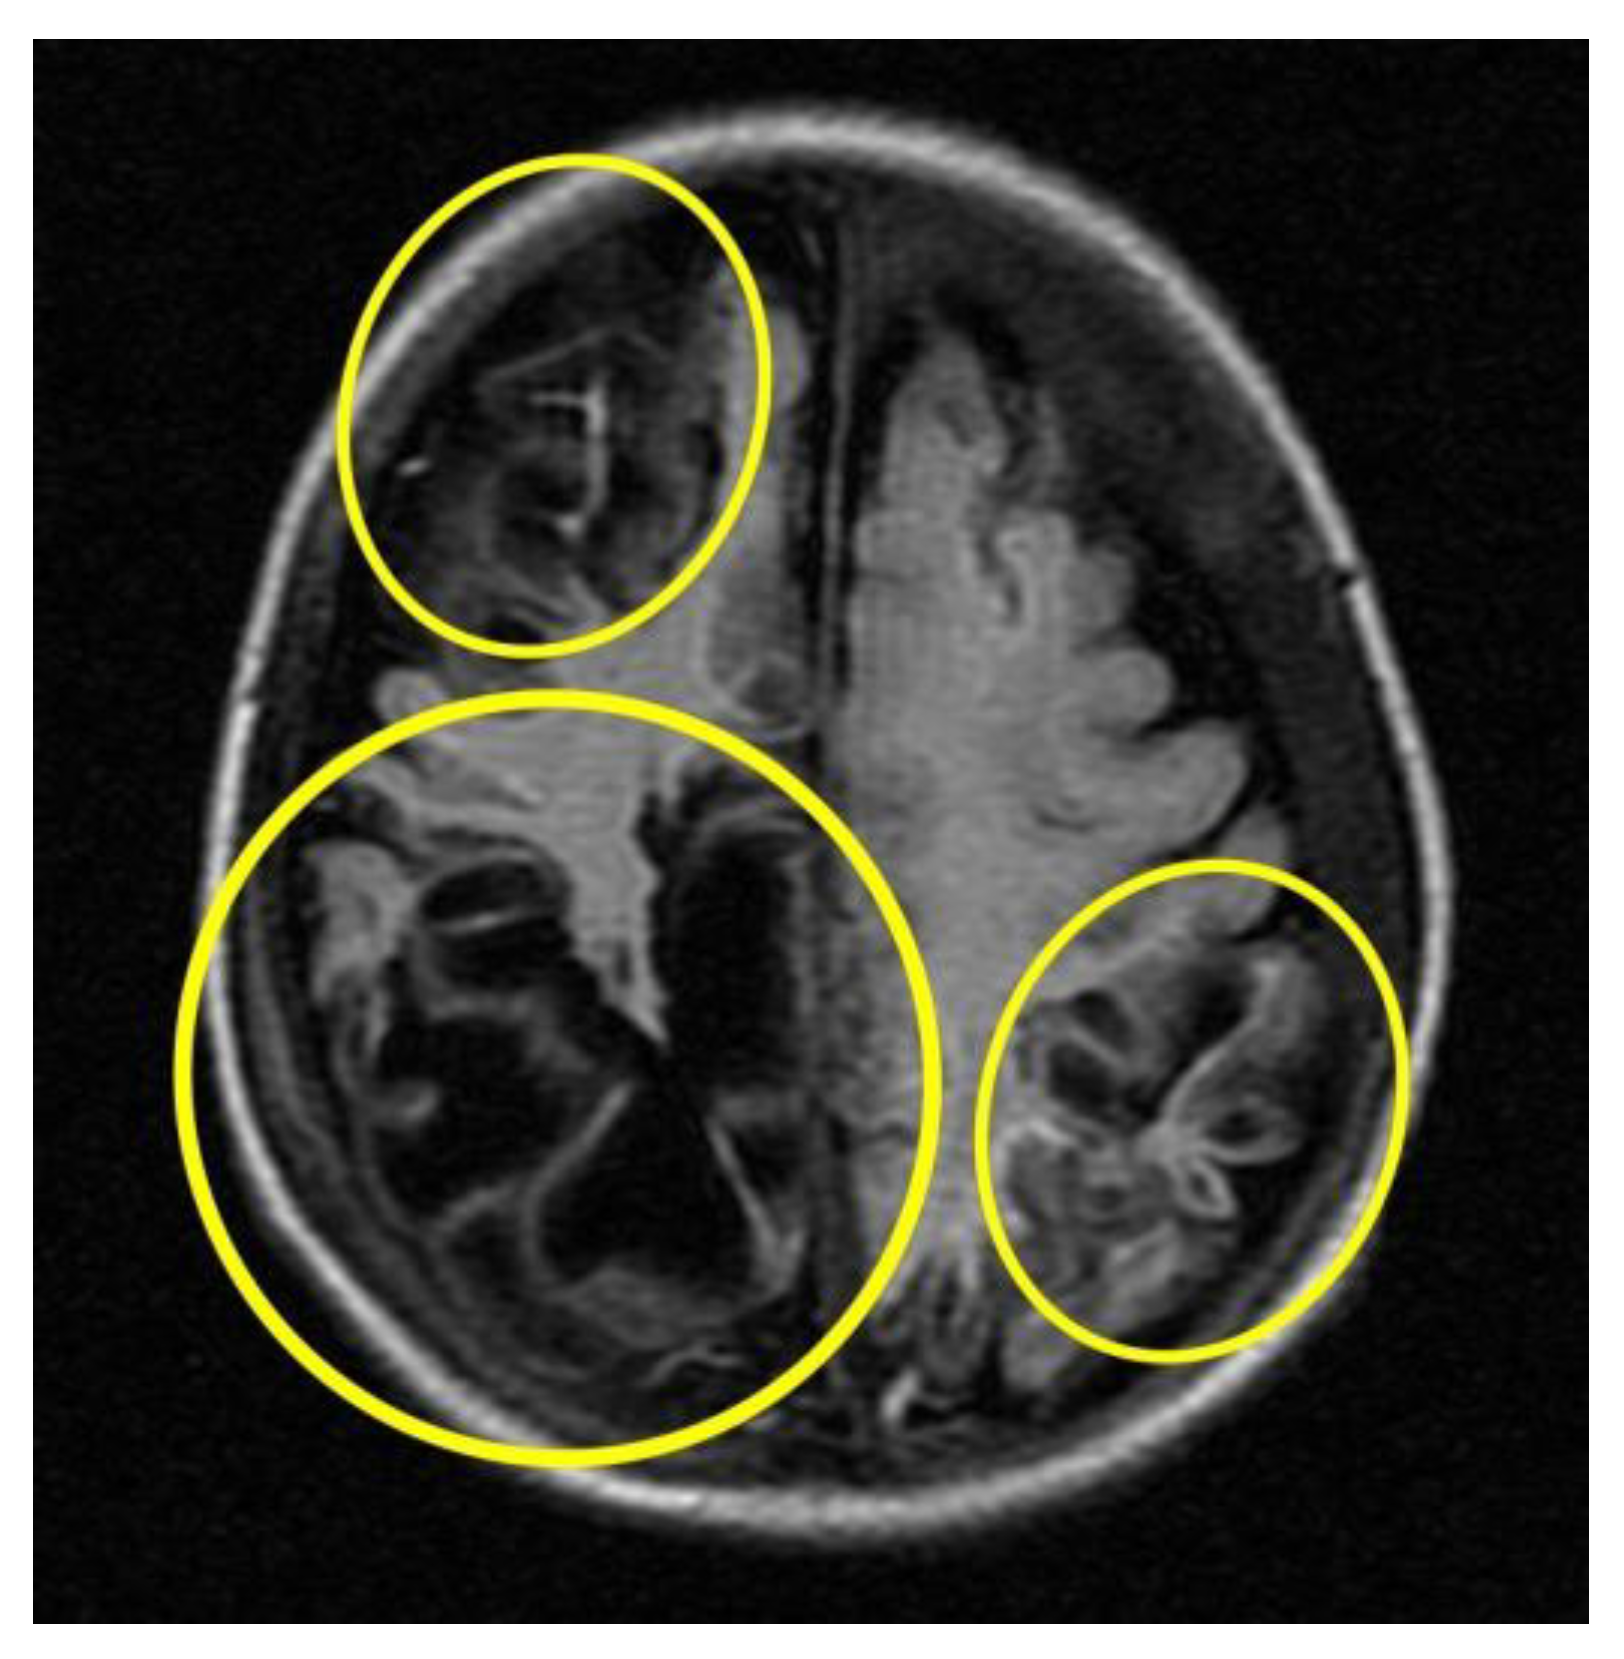

Subsequent instrumental investigations were performed on the baby to assess cranio-encephalic outcomes. In particular, the MRI (Figure 5) performed about a month after the presumed trauma revealed a picture characterised by cortical atrophy and cystic evolution of the brain parenchyma, mainly in the occipital region bilaterally.

MRI cortical atrophy and cystic evolution of the brain parenchyma (circles in yellow).